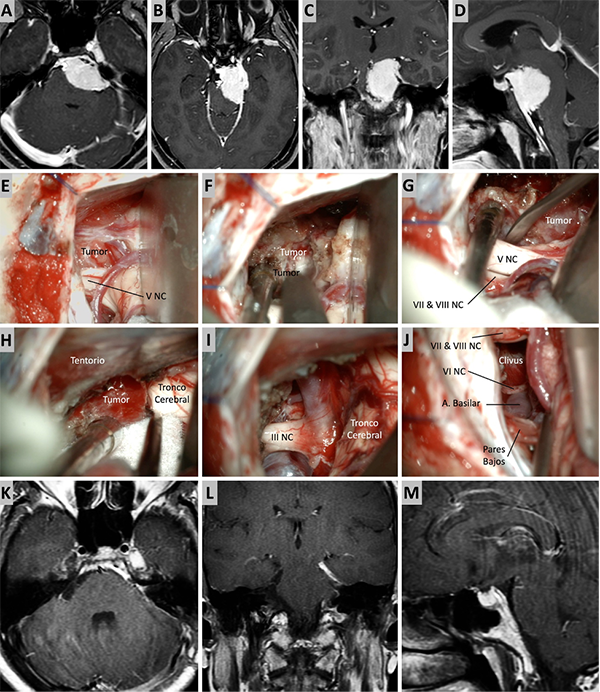

Figura 3. Caso ilustrativo #1. MRPC con implantación petroclival, extensión a la fosa media y compromiso de la incisura tentorial. Paciente con audición conservada. A. Corte axial sobre la región clival media. B. Corte axial sobre la región clival superior. Corte Coronal. D. Corte sagital donde se observa el efecto compresivo sobre el tallo cerebral. E-J. Se realizo un abordaje retrosigmoideo. K-N. Se muestra las imágenes en distintos cortes con el resultado quirúrgico. Residuo tumoral incipiente sobre la incisura tentorial.